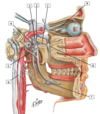

1

Q

1

A

1 - stylohyoid muscle

2

Q

1

A

1 - Digastric muscle

6

Q

1

A

1 - trochlear nerve (IV)

7

Q

2

A

2 - ophthalmic nerve (V1)

8

Q

3

A

3 - optic nerve (ii)

9

Q

4

A

4 - oculomotor nerve (iii)

10

Q

5

A

5 - abducent nerve (VI)

11

Q

6

A

6 - trigeminal (semilunar) ganglion

12

Q

7

A

7 - frontal nerve

13

Q

8

A

8 - lacrimal nerve

14

Q

9

A

9 - supra-orbital nerve